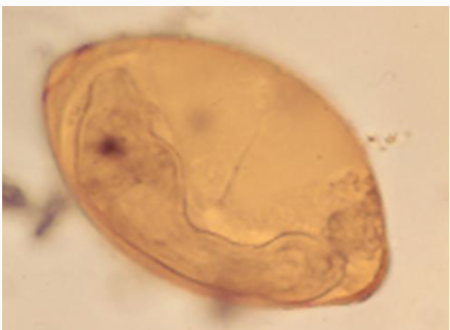

Fasciola hepatica egg

120-150 microns in length

• oval in shape

• yellow brown in colour

• operculum at one end (barely visible)